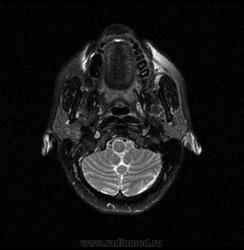

06.06.2011 МРТ - головы и шеи.

Пацентка 36 лет, с жалобами на припухлось в околоушной области справа.

В глубокой доле  правой околоушной железы  на фоне неизмененной паренхимы зона  гетерогенного по Т2, гипоинтенсивного по Т1  с единичными гиперинтенсивными включениями.При контрастировании- накопление контраста диффузное неоднородное и по периферии.Рискну предположить злокачественное образование ( аденокарцинома) с низкой степенью злокачественности( есть капсула, экспансивный рост).Сильно не расстреливайте.

Проблема в том, что перед челюстно-лицевым хирургом стоит распространенность любого объемного процесса, в данном случае все упирается в возмможную травму лицевого нерва и конечно же с дальнейшим его парезом, а ведь женщина  еще молодая. Образование имеет тонкостенную оболочку, по структуре неоднородно, с наличием кальцината, при этом МР-сигнал от окружающих анатомических структур(как костных так и мышечных) не изменен, т.е. об инфильтративном росте речи не идет, в какой то степени доброкачественное. В конкретном случае лицевой нерв с ретромандибулярной веной просто несколько оттеснен.

По гистологии аденома околоушной слюнной железы, но после удаления пока сохраняется парез лицевой мускулатуры, возможно временный.